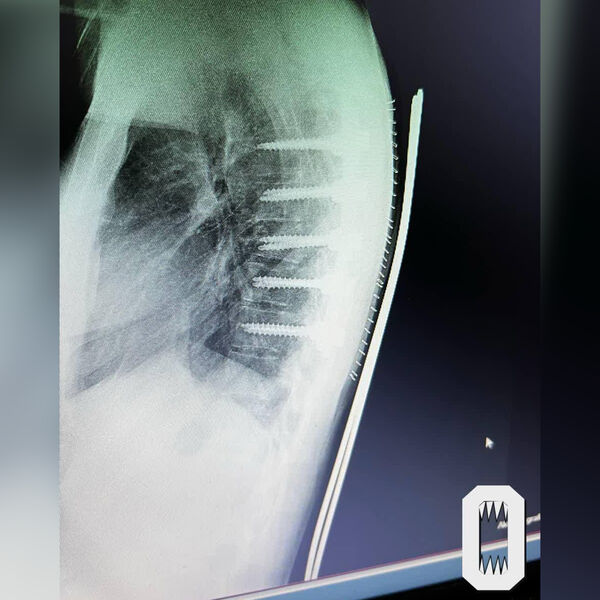

Как рассказала 21-летняя потерпевшая, в августе 2024 года она отправилась на отдых в Бодрум по путевке туроператора Anex. Девушка утверждает, что по приезде приобрела у представителя компании билет на экскурсию, на которой предполагалась прогулка по реке Дальян и осмотр ущелья. 8 августа, в день тура, водитель автобуса, в котором находилась девушка, не справился с управлением и улетел в кювет. 21-летней россиянке потребовалась помощь скорой: ее доставили в больницу города Милас, где диагностировали ей перелом позвонка грудного отдела. Во время операции ей установили титановые штифты.